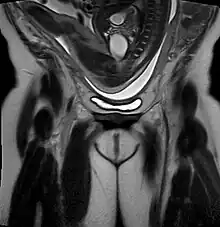

- Uterus arcuatus 22.6%

- Uterus unicornuatus 33.3%

- Uterus bicornuatus 34.8%

- Uterus didelphys 30–41%

- Uterus septus 45.8%